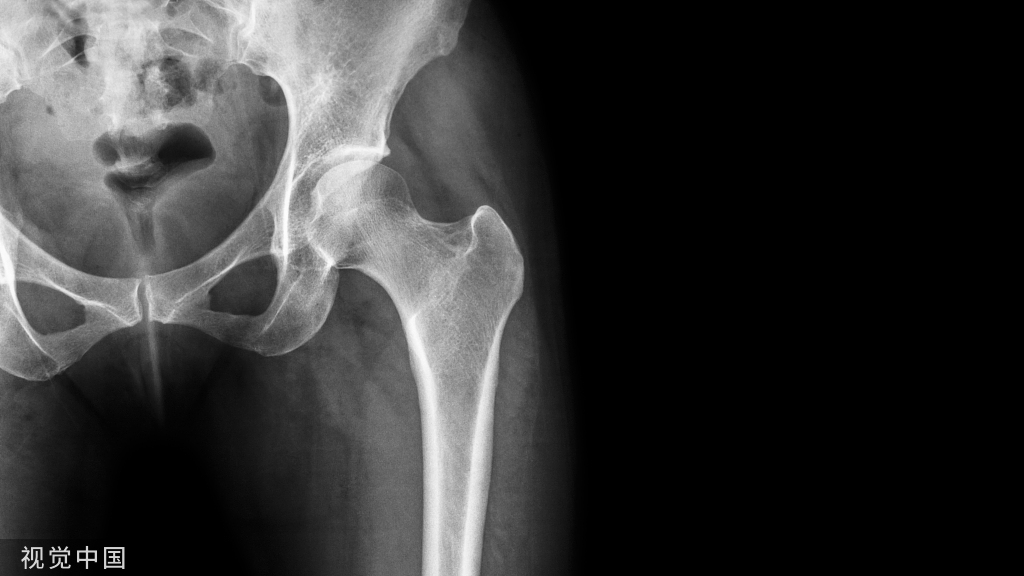

关于HO的发生率,多数研究报道为10%~20%。无论是中枢神经损伤性还是四肢创伤性HO,最好发是髋关节,其次是肘、膝、肩,几乎不累及腕、踝、手、足这样的小关节。

脊髓损伤患者的HO极少发生于上肢关节。创伤性HO可位于关节旁或将关节包绕,而神经损伤性HO则往往位于关节旁。在创伤骨科中,尤以髋臼骨折和肘关节骨折最为多见。关节置换术后以及严重的长骨骨折后异位骨化发病率为3%~20%。

髋臼骨折和肘部骨折所致异位骨化最为常见,髋臼骨折内固定术后大约40%患者形成异位骨化。Guo等推荐髋臼骨折手术采用粗隆翻转或者后侧入路,异位骨化在粗隆翻转、前路手术及后路手术的发生率分别为33.3%、42.1%和36.9%